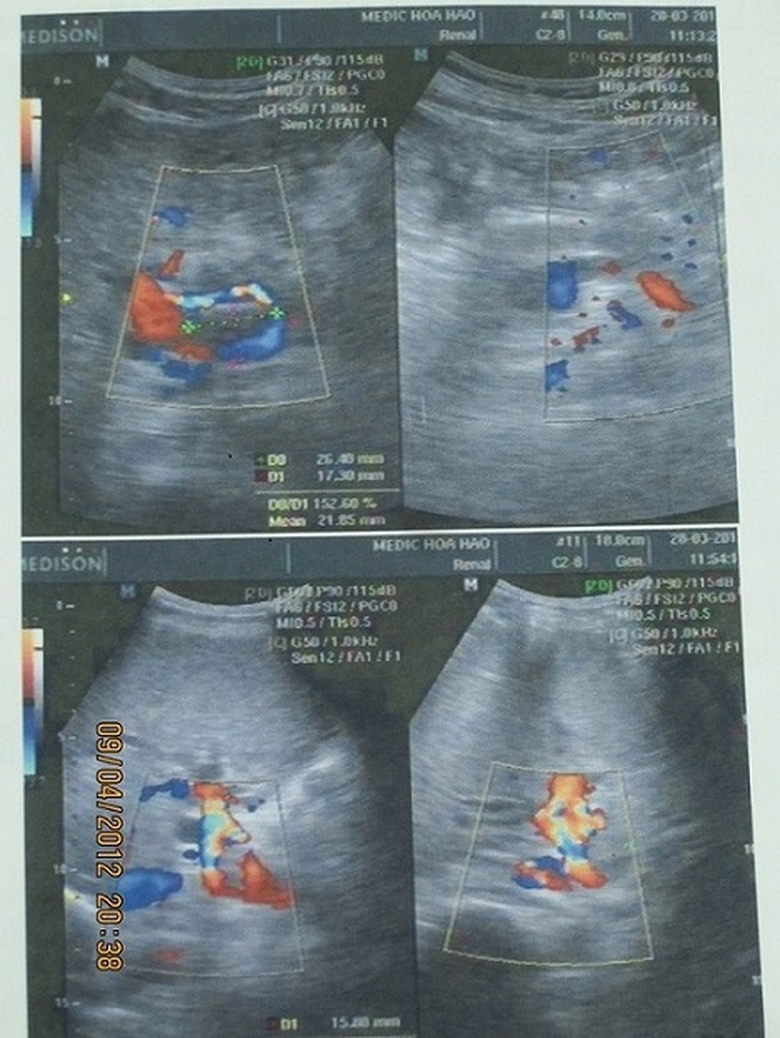

Một trong những trường hợp thực tế được hưởng lợi từ phương pháp điều trị ung thư gan bằng nấm lim xanh kết hợp với Tây y là trường hợp của ông Trần Tiến Khởi (1958, xã Cát Tiến, huyện Phù Cát, Bình Định). Đầu năm 2012, khi tới bệnh viện kiểm tra, ông Khởi được các bác sỹ chẩn đoán mắc bệnh ung thư biểu mô tế bào gan giai đoạn đầu. Các bác sỹ đã áp dụng phương pháp TOCE tiêm hóa chất nhằm tiêu diệt các tế bào ung thư. Trải qua 2 lần tiêm hóa chất chữa ung thư gan trong 6 tháng, kết hợp với sử dụng một số bài thuốc nam trong đó có nấm lim xanh, các bác sỹ kiểm tra và xác nhận các khối u trong cơ thể ông đã thu nhỏ gần hết và không di căn sang các cơ quan khác trong cơ thể.

Siêu âm gan bệnh nhân Trần Tiến Khởi trong quá trình điều trị ung thư gan với nấm lim xanh có diễn biến tích cực. |